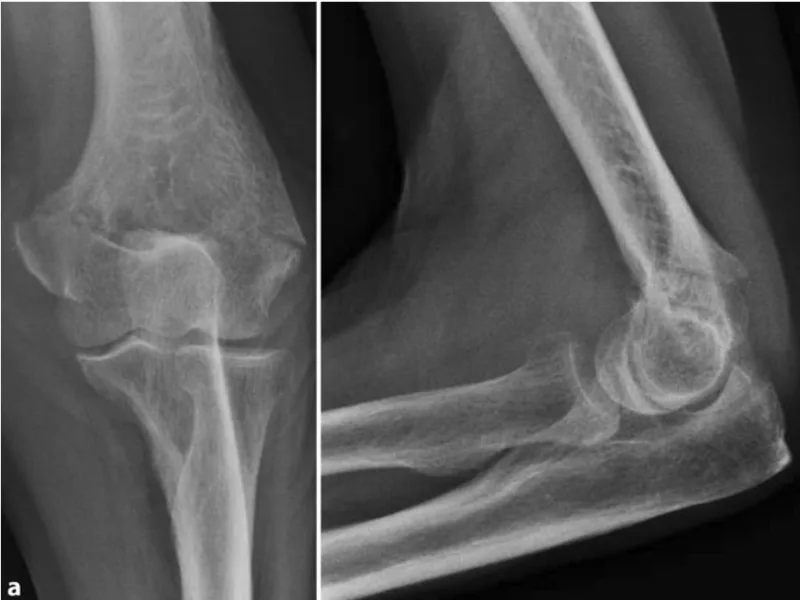

骨折を疑って, 肩関節, 肘関節, 手関節のX線写真を撮像することに.

その結果, 上腕骨の通顆骨折でした.

ズレがほとんどなかったので, ギプスシーネを巻いて, 固定.